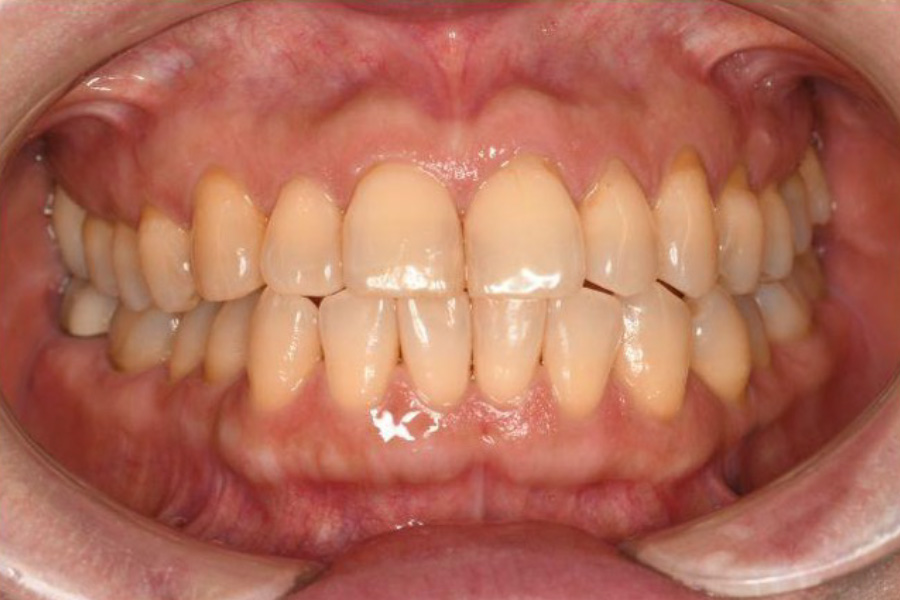

治療後

| 治療内容 | 全顎治療:歯周病治療、根管治療、 歯肉弁剥離掻爬術(フラップ手術)、 セラミック治療、ダイレクトボンディング |